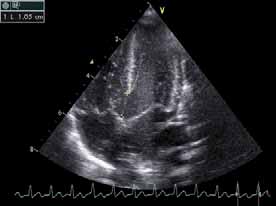

- Shunts gauche – droite dominant la scène.

- Communication interventriculaire (CIV) large.

- Persistance du canal artériel.

- Canal atrioventriculaire (chez le trisomique 21).

- Risque d’hypertension artérielle pulmonaire (HTAP) irréversible si le shunt est opéré trop tard. Chirurgie en général dans la première année de vie (figures 3 et 4).